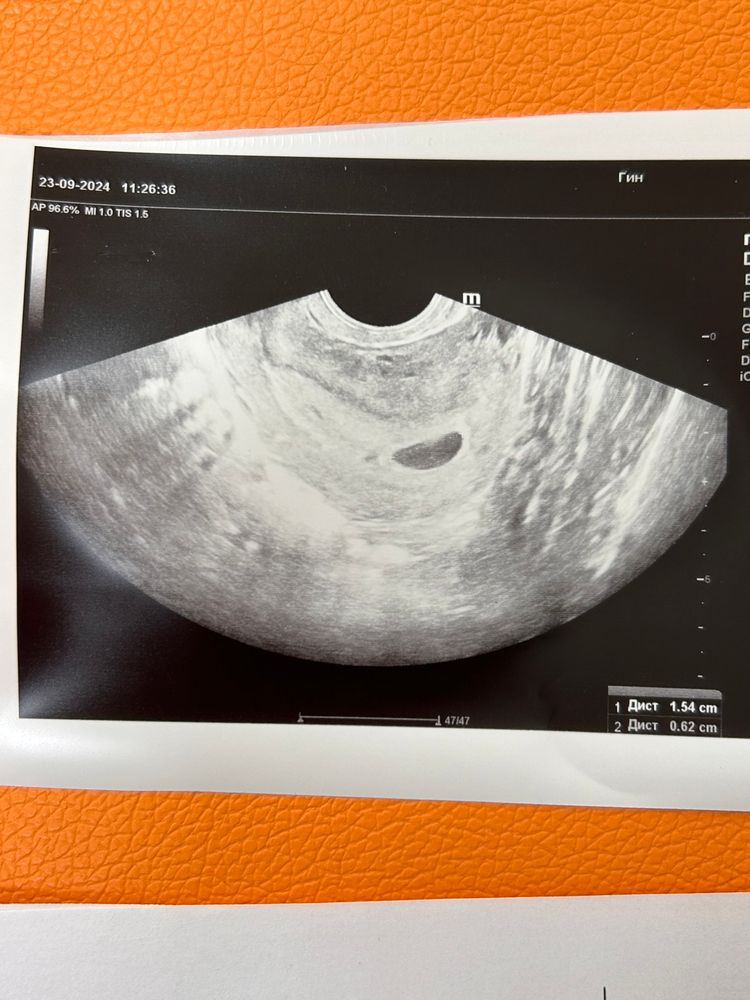

Плодный мешок узи

Плодный мешок узи 119 фотографий